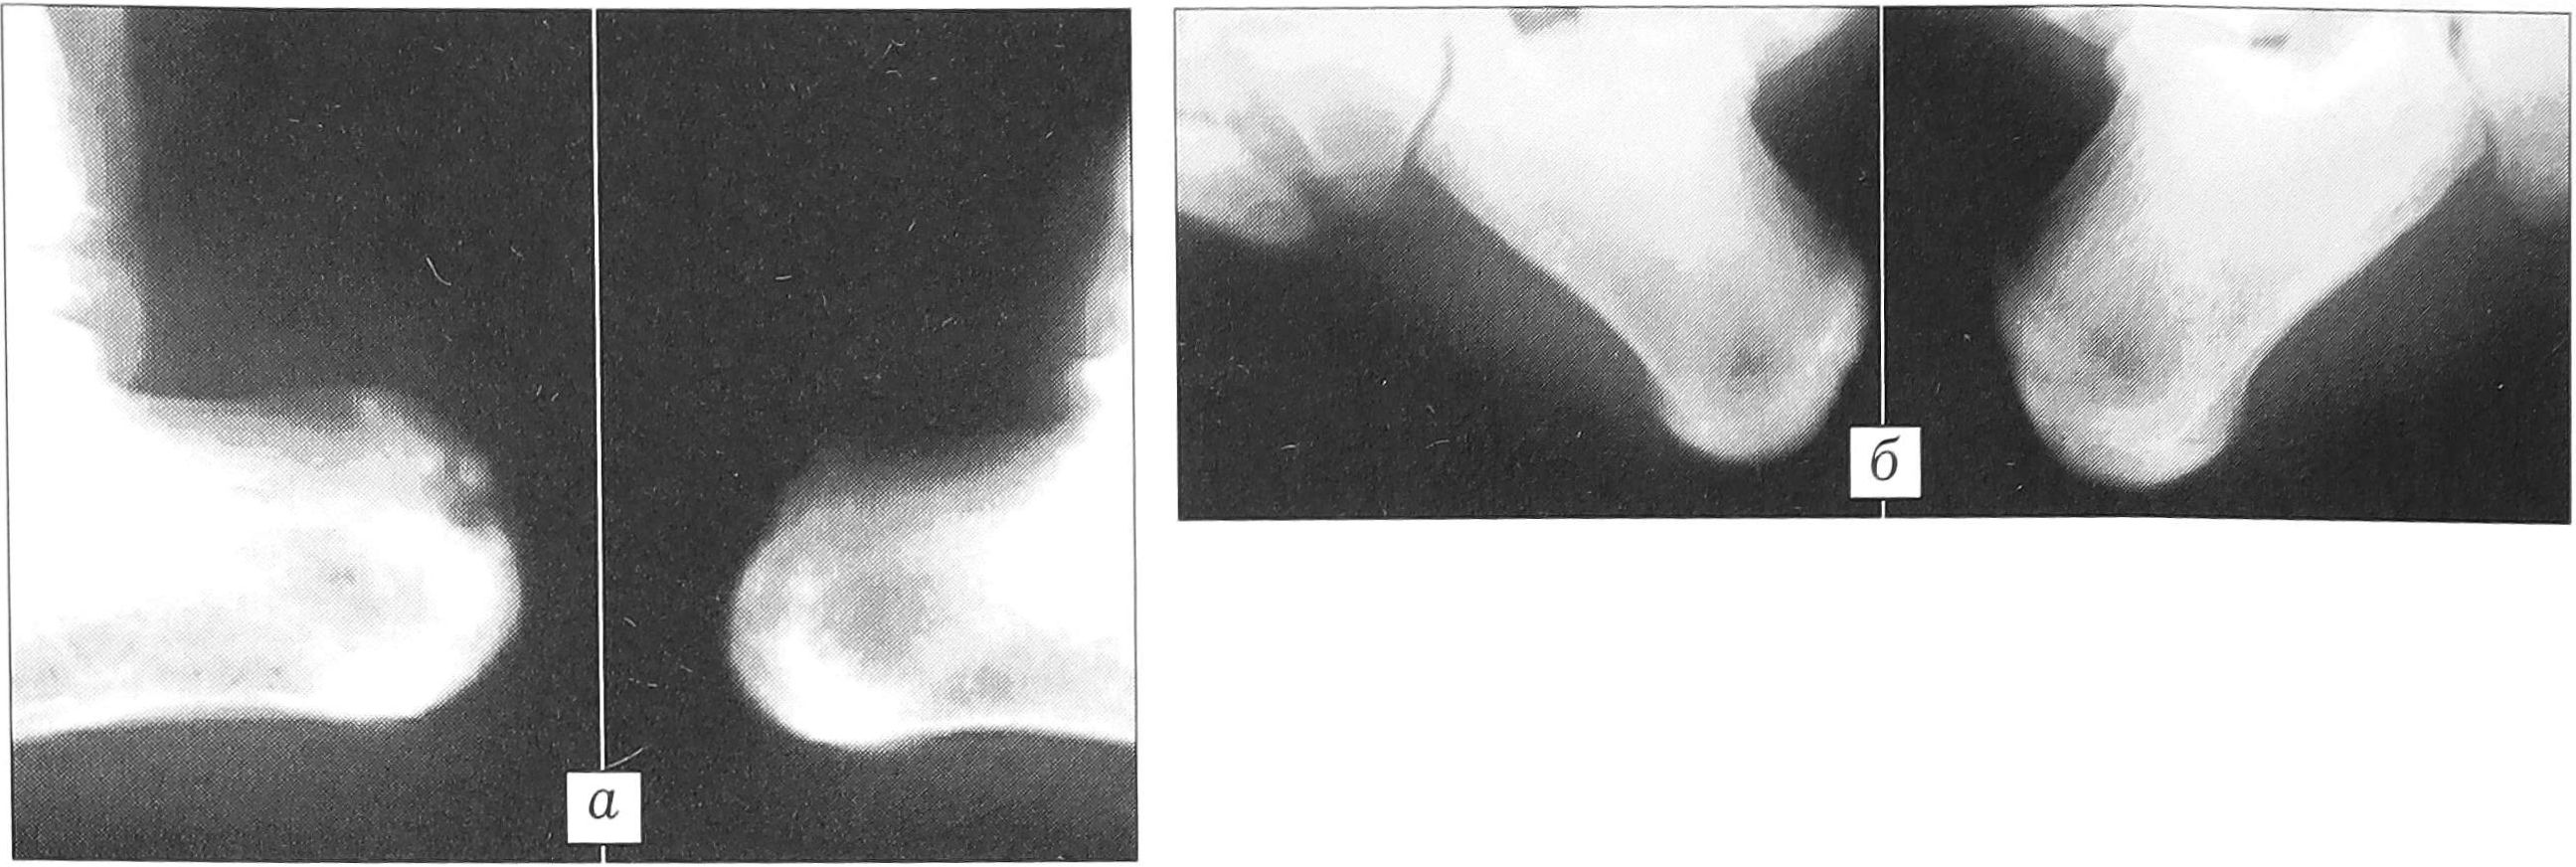

Клинический пример. Больной К., 14 лет. Диагноз: болезнь Хаглунда—Шинца справа. В течение 3 лет беспокоят боли в пяточной области, возникающие при ходьбе и отмечаемые при пальпации. На протяжении года проводились курсы консервативной терапии, не давшие эффекта. Рентгенологически определяется картина остеохондропатии бугра пяточной кости со свободно лежащим костным фрагментом (рис. 1, а). Произведена туннелизация области остеохондропатии и введен биоактивный имплантат с глюконатом кальция и оротовой кислотой. Иммобилизация гипсовой лонгетой продолжалась 14 дней. Болевой синдром купирован в течение 2 нед, рентгенологическая картина нормализовалась через 6 мес (рис. 1, б).

Рис. 1. Больной К. 14 лет. Диагноз: болезнь Хаглунда—Шинца справа. а — рентгенограммы до операции: дефект области бугра правой пяточной кости; б — рентгенограммы через 6 мес после операции: практически полное закрытие дефекта.